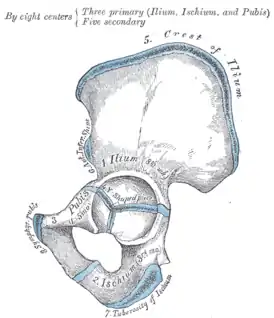

Тазовая кость (лат. os coxae) — это обозначение для парной кости правой и левой, которые относятся к поясу нижних конечностей, а вместе с крестцом и копчиком образуют таз. Используется также название безымянные кости. Каждая из тазовых костей в свою очередь образована тремя составляющими: подвздошной костью, седалищной костью и лобковой костью, которые соединяются посредством хряща в области вертлужной впадины, служащей местом соединения тазовой кости с бедренной. В возрасте 14-16 лет эти три кости срастаются, образуя единую тазовую кость.

Подвздошная кость (лат. os ilium) составляет ближайшую к позвоночнику часть пояса задних конечностей или таза, сочленяющуюся с крестцовыми позвонками. Она ясно выражена уже у амфибий. У человека она сочленяется крестцовой костью, являющейся результатом слияния 5 позвонков, и в области вертлужной впадины, служащей для помещения головки бедра, срастается с двумя другими тазовыми костями: седалищной и лобковой. Верхний край подвздошной кости человека закруглён, передний и задний образуют по два выступа (лат. spinae anterior superior, ant. inferior, posterior superior, post. inferior), а на своей внутренней и наружной поверхности она имеет изогнутое линейное возвышение (linea arcuata inferior et exterior).

Седалищная кость (лат. os ischii) — одна из костей пояса задних или нижних конечностей, иначе таза. Она ясно выражена уже у амфибий. У человека она состоит из следующих частей: тело, которое соединяется сверху с подвздошной костью, а спереди с лобковой горизонтальной ветвью и вместе с этими костями образует тазовую кость (os coxae). В месте соединения этих костей находится вертлужная впадина (acetabulum) для приёма бедренной головки. От тела вниз на задней части отходит нисходящая ветвь (ramus descendens), образующая на нижнезаднем углу седалищный бугор (Tuberculum ossis ischii) и продолжающаяся вперёд и вверх в виде восходящей ветви (ramus ascendens). Последняя с нисходящей ветвью лобковой кости, и таким образом между телом седалищной кости, её обеими ветвями и обеими ветвями лобковой образуется овальной формы отверстие (foramen obturatum sivo ovale).

Лобковая кость (лат. os pubis) — одна из трёх костей, образующих при сращении тазовую кость. Состоит из тела и двух ветвей. Ветви и тело лобковой кости образуют запирательное отверстие (foramen obturatoris), закрытое запирательной мембраной. Две лобковые кости, срастаясь, образуют переднюю стенку таза.